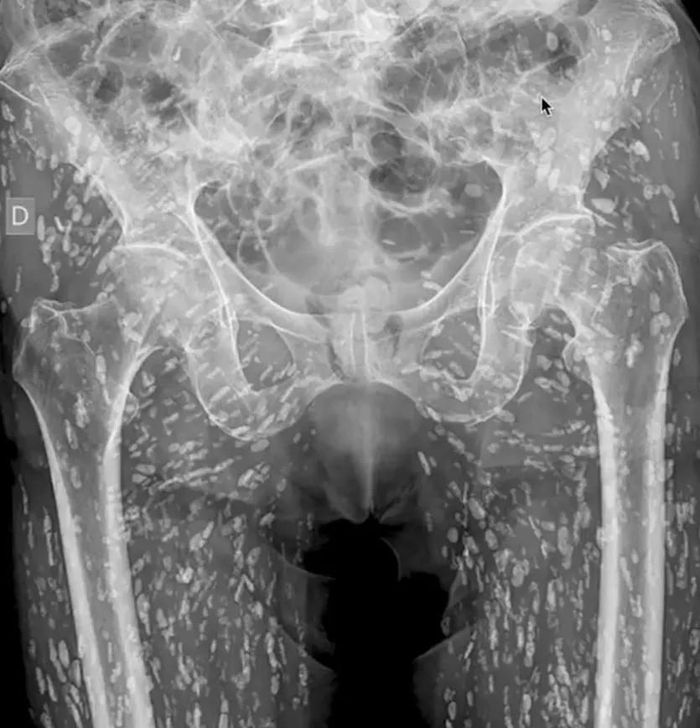

Bác sĩ người Mỹ Sam Ghali đã chia sẻ thông tin sức khỏe của người đàn ông giấu tên và nói rằng đó là "một trong những phim chụp X-quang đáng sợ nhất mà tôi từng thấy". Vị bác sĩ nói thêm: "Đây là các nang ấu trùng của sán dây taenia solium còn được gọi là sán dây lợn".

Tình trạng đó xảy ra khi một người ăn thịt lợn sống hoặc chưa nấu chín dẫn tới nhiễm sán trong đường tiêu hóa. Những nang này có thể di chuyển khắp cơ thể con người. Ở bệnh nhân trên, các nang ấu trùng đã di chuyển rất nhiều đến các mô cơ và mô mềm ở hông và chân.

Người đàn ông tình cờ phát hiện ra bệnh khi đi chụp X-quang do bị ngã và đau hông. Trong trường hợp này, các nang không gây ra vấn đề đe dọa tính mạng. Nhưng trong một số ca, nang ấu trùng có thể gây ra bất ổn nghiêm trọng, đặc biệt khi di chuyển tới não. Bệnh ấu trùng sán dây thần kinh có nguy cơ dẫn đến các triệu chứng như đau đầu, lú lẫn, co giật, thậm chí tử vong.

Phim chụp X-quang của người đàn ông nhiễm sán dây lợn. Ảnh: X